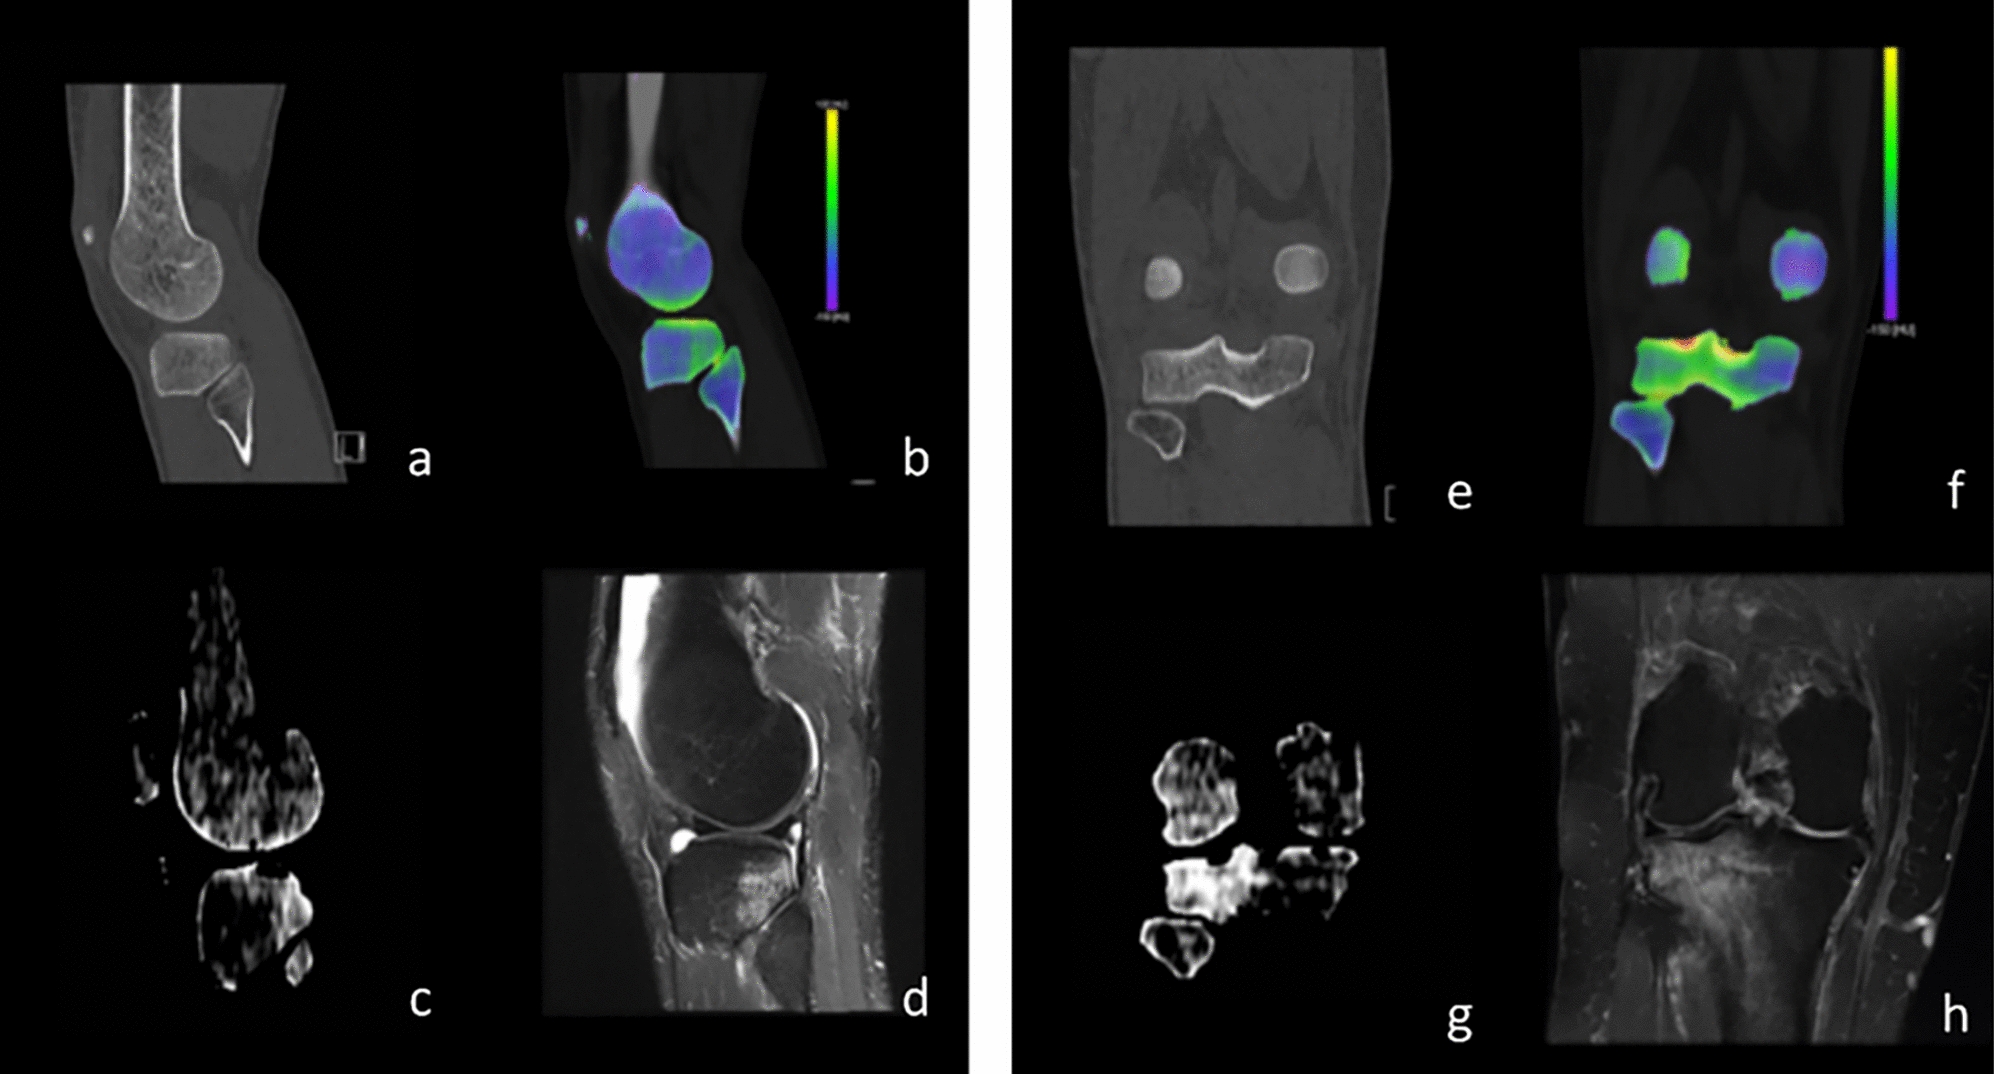

Predicting disease-free survival in locally advanced rectal cancer using a prognostic model based on pretreatment b-value threshold map and postoperative pathologic features

Disease-free survival (DFS) after neoadjuvant chemoradiotherapy (nCRT) is an important factor in affecting the quality of ...